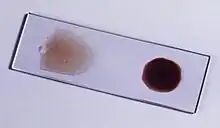

Malaria is usually confirmed by the microscopic examination of blood films or by antigen-based rapid diagnostic tests (RDT). Microscopy – i.e. examining Giemsa-stained blood with a light microscope – is the gold standard for malaria diagnosis.[33] Microscopists typically examine both a "thick film" of blood, allowing them to scan many blood cells in a short time, and a "thin film" of blood, allowing them to clearly see individual parasites and identify the infecting Plasmodium species.[33] Under typical field laboratory conditions, a microscopist can detect parasites when there are at least 100 parasites per microliter of blood, which is around the lower range of symptomatic infection.[62] Microscopic diagnosis is relatively resource intensive, requiring trained personnel, specific equipment, electricity, and a consistent supply of microscopy slides and stains.[62]

In places where microscopy is unavailable, malaria is diagnosed with RDTs, rapid antigen tests that detect parasite proteins in a fingerstick blood sample.[62] A variety of RDTs are commercially available, targeting the parasite proteins histidine rich protein 2 (HRP2, detects P. falciparum only), lactate dehydrogenase, or aldolase.[62] The HRP2 test is widely used in Africa, where P. falciparum predominates.[33] However, since HRP2 persists in the blood for up to five weeks after an infection is treated, an HRP2 test sometimes cannot distinguish whether someone currently has malaria or previously had it.[62] Additionally, some P. falciparum parasites in the Amazon region lack the HRP2 gene, complicating detection.[62] RDTs are fast and easily deployed to places without full diagnostic laboratories.[62] However they give considerably less information than microscopy, and sometimes vary in quality from producer to producer and lot to lot.[62]